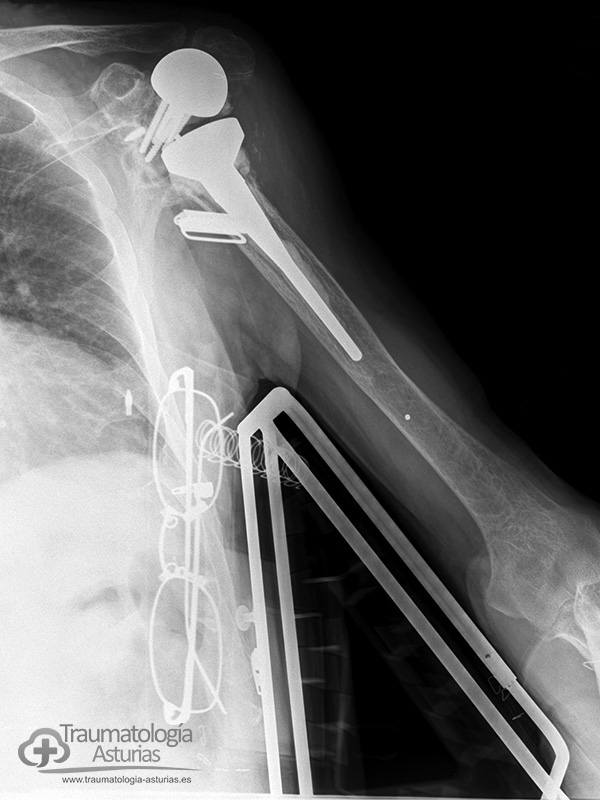

Las cirugías protésicas repetidas en el hombro procovan un déficit del tejido óseo, sobre todo glenoideo, que requiere el uso de injertos óseos y el uso de técnicas quirúrgicas originales para dar estabilidad primaria a la articulación como en este caso un tornillo guia canulado a la fosa supraespinosa y el tope óseo acromio-coracoideo apoyado en placa de osteosíntesis